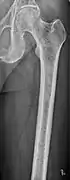

The diagnostic examination of a person with suspected multiple myeloma typically includes a skeletal survey. This is a series of X-rays of the skull, axial skeleton, and proximal long bones. Myeloma activity sometimes appears as "lytic lesions" (with local disappearance of normal bone due to resorption). And on the skull X-ray as "punched-out lesions" (pepper-pot skull). Lesions may also be sclerotic, which is seen as radiodense.[47] Overall, the radiodensity of myeloma is between −30 and 120 Hounsfield units (HU).[48] Magnetic resonance imaging is more sensitive than simple X-rays in the detection of lytic lesions, and may supersede a skeletal survey, especially when vertebral disease is suspected. Occasionally, a CT scan is performed to measure the size of soft-tissue plasmacytomas. Bone scans are typically not of any additional value in the workup of people with myeloma (no new bone formation; lytic lesions not well visualized on bone scan).

Multiple myeloma in the upper arm